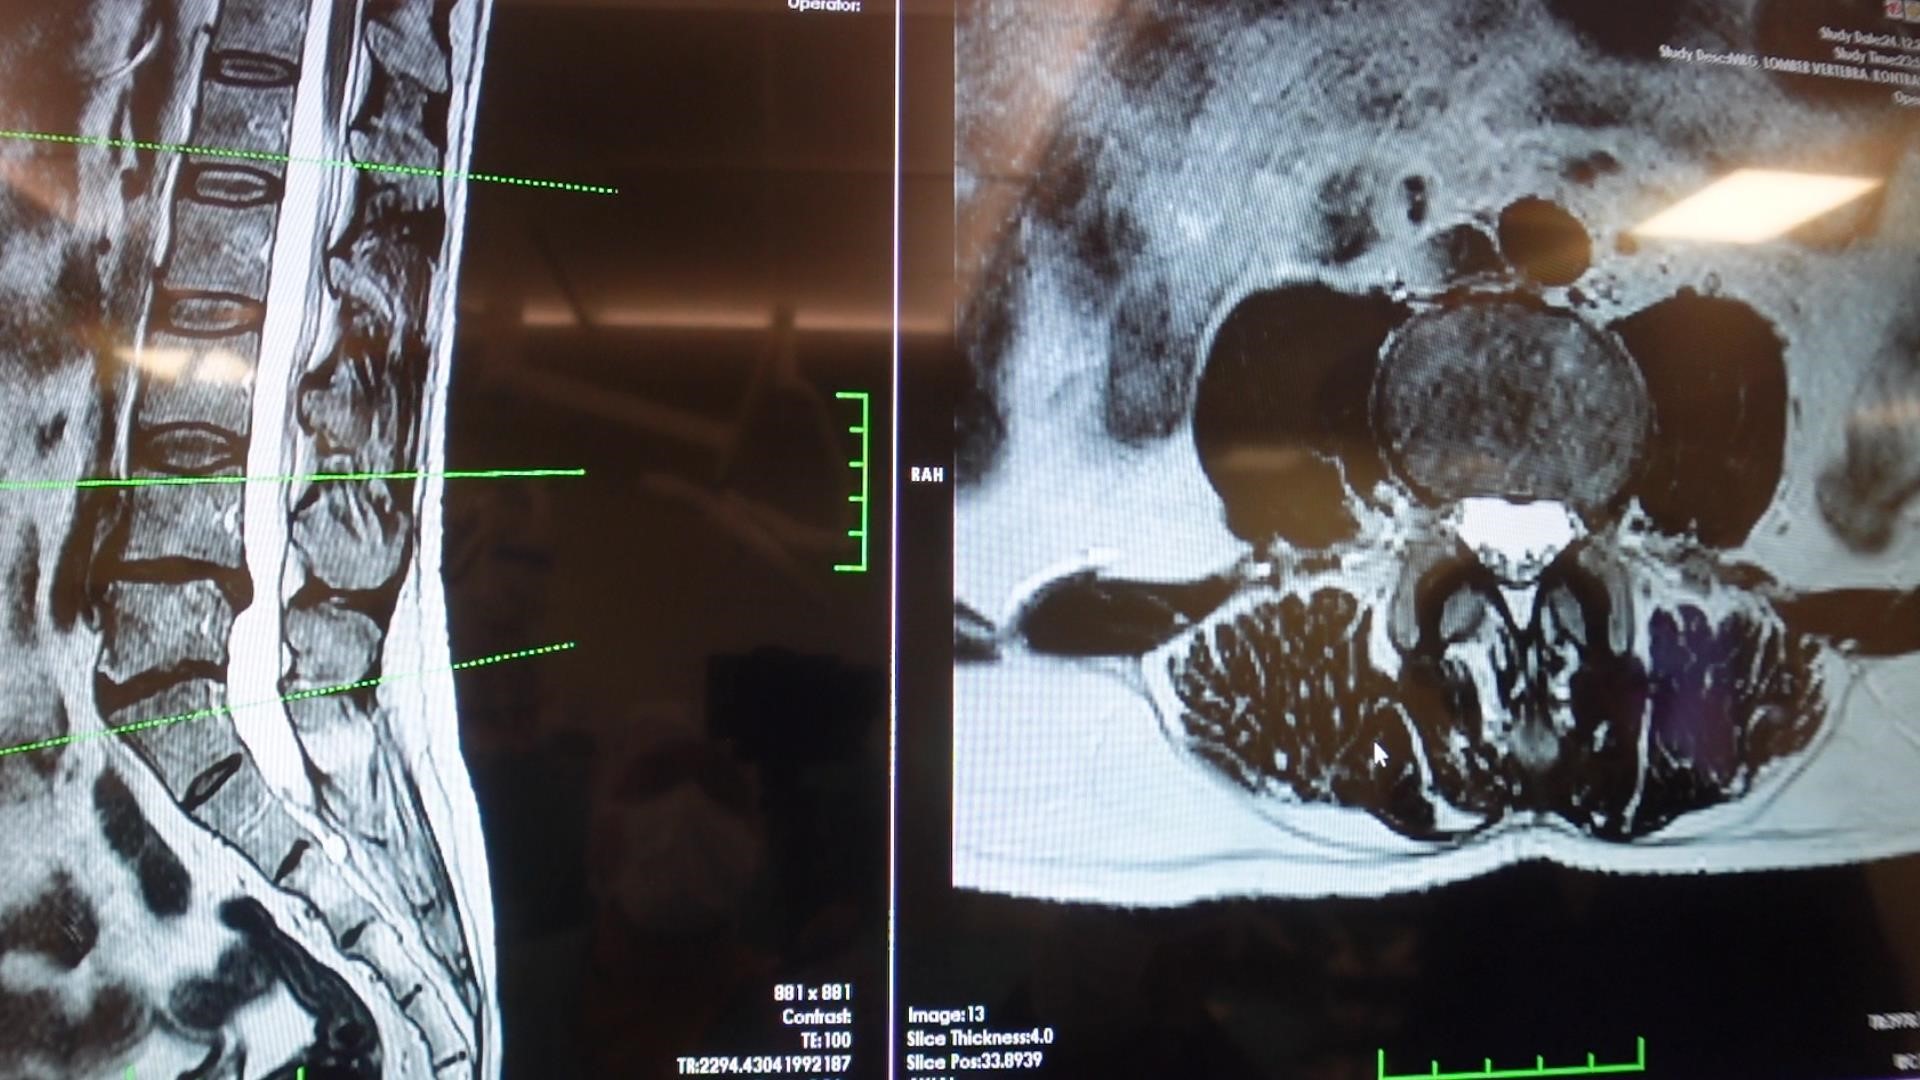

Elazığ Fırat Üniversitesi Hastanesi Beyin ve Sinir Cerrahisi Anabilim Dalı Başkanı Prof. Dr. Fatih Serhat Erol, bel fıtığı hastalığı hakkında açıklamalarda bulundu. Beyin ve sinir cerrahisi pratiğinde sık karşılaşılan hasta gruplarından birinin omurga hastaları olduğunu belirten Prof. Dr. Erol, "Boyun ve sırt omurlarının yanı sıra en çok bel bölgesiyle ilgili sorunlar görülüyor. Bel fıtığı önemli bir hastalıktır. Bel ağrılarının büyük bir kısmının bel fıtığından değil, mekanik bel ağrısından kaynaklanıyor. Mekanik bel ağrısının kaslar, eklemler, iskelet sistemi ve bu yapıları birbirine bağlayan bağların uzun süreli zorlanması sonucu ortaya çıkmaktadır. Bu durumun hastalarda şiddetli bel ağrısına neden olabilir. Mekanik bel ağrısının bel fıtığı ile karıştırılmaması gerekiyor.

Bel fıtığına kıyasla mekanik bel ağrıları çok daha sık görülüyor. Bir diğer önemli hasta grubu ise omurilik kanal darlığı olan hastalardır. Bu hastalıkta dejeneratif süreçler sonucunda omurilik kanalında ve sinir köklerinin geçtiği kemik kanallarda daralma ve kireçlenme meydana geliyor. Bu durumun omurilik ve sinir köklerinde sıkışmaya yol açar. Hastaların ayakta dururken ya da yürürken bel, kalça ve bacaklara yayılan şiddetli ağrılar hissettiğini, yürüyüş mesafesi arttıkça oturup dinlenme ihtiyacı duyarlar. Tedavi sürecinin doğru tanıya göre belirleniyor. Bel ve bacak ağrısı şikayeti olan hastaların mutlaka bir beyin ve sinir cerrahisi uzmanına başvurması gerekiyor. Hastaların şikayetlerinin dinlenmesi, gerekli muayene ve tetkiklerin yapılmasının ardından hastalıkların birbirinden ayırt edilebildiğini ve buna uygun tedavi planının oluşturulur" cümlelerini kullandı.